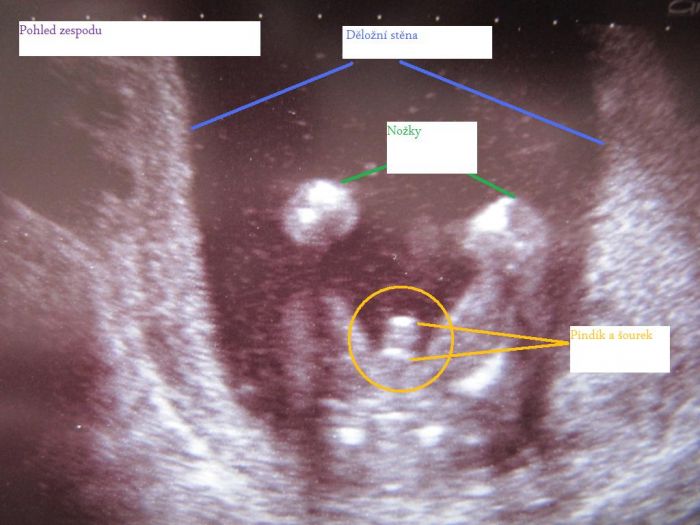

MeIDo, myslím, že druhému screeningu se říká Triple test. A ve 20.tt je velký ultrazvuk, ale nejsem si tím vůbec jistá. Junýsku, pro tebe (a ostatní, co si nejsou jisté) vkládám tu třetí fotku s vytvořeným popiskem

Snad jsem to pochopila správně a nepopletla to